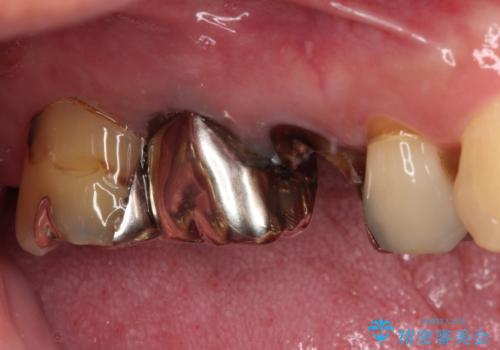

もげてしまった奥歯 オールセラミッククラウンでの補綴治療

- 食事中に歯がもげてしまったとのことで来院された患者様です。

レントゲン写真から、特に大きなむし歯などは認められませんでしたが、根管治療があまり十分に行われているとは言えない状態でした。

まずは仮歯を装着し、根管治療を行った上で土台を植立し、オールセラミッククラウンにて補綴治療を行うこととしました。